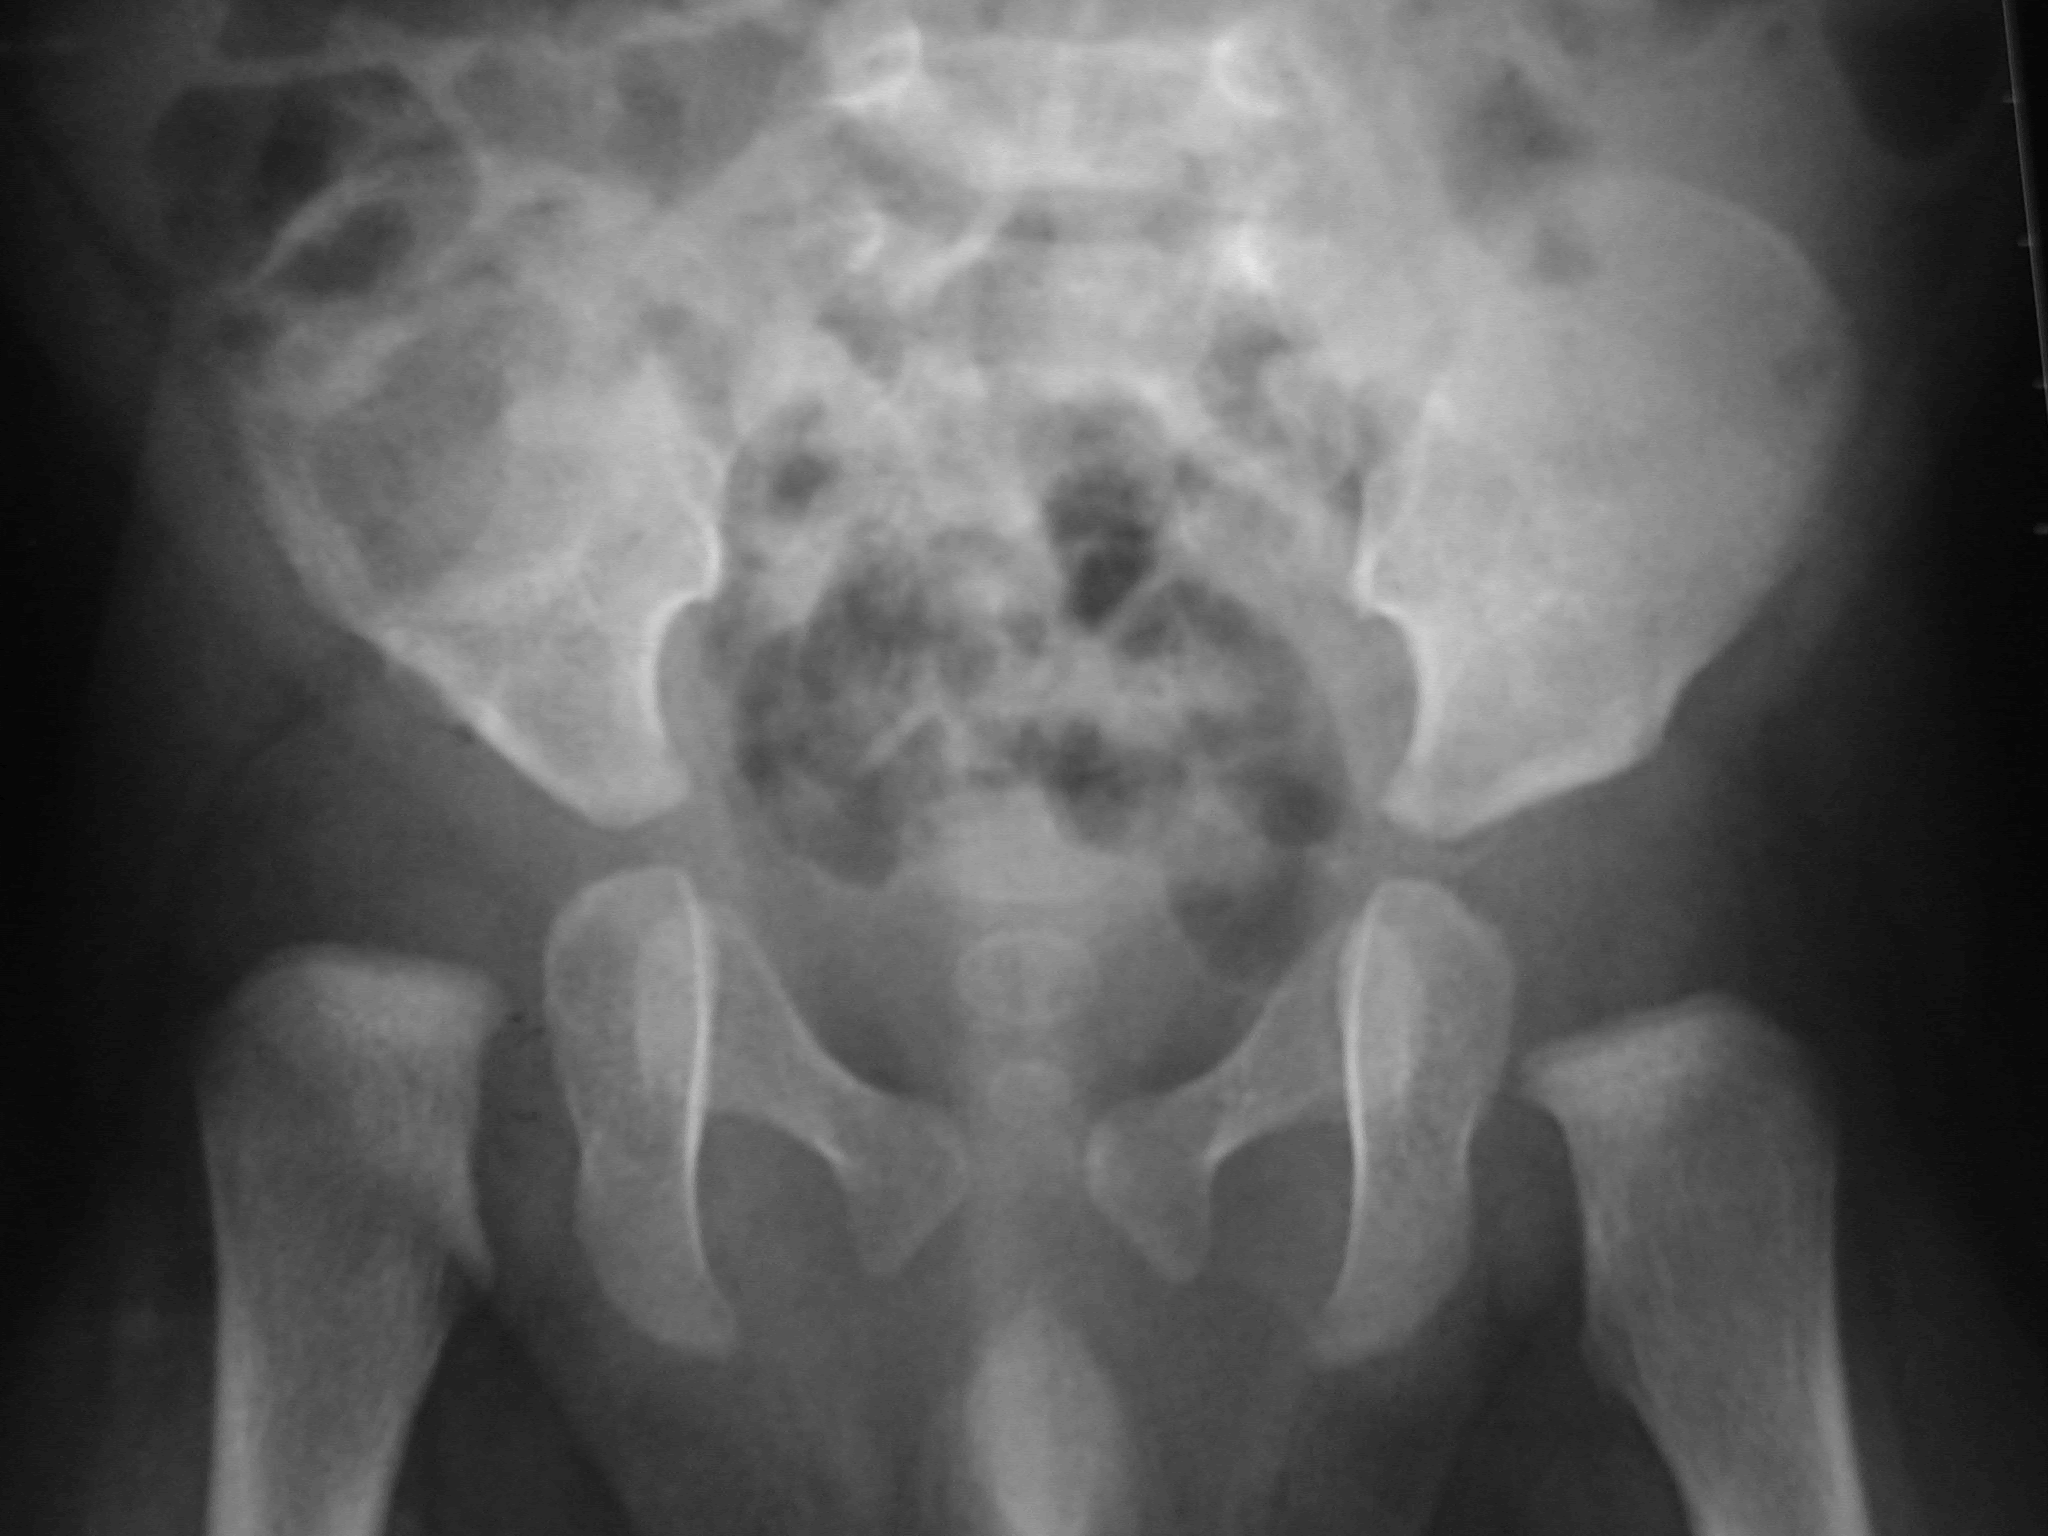

J'ai juste pris un coup de massue quand je l'ai entendue me dire que mon Bébé avait une dysplasie de la hanche De retour chez nous, Mon fils de 1 mois a une luxation de la hanche gauche, le spécialiste doit lui poser un harnais de Pavlik dans la matinée J'appréhende beaucoup tout ce qui va nous arriver et notamment, le fait de devoir arrêter mon allaitement maternel, fauteLa luxation congénitale de la hanche estelle traitée ?Luxation de hanche droite chez une fille de 13 mois (a) Une chirurgie est réalisée, la tête est repositionnée et les défauts au niveau du bassin et du fémur sont corrigés (b) La radiographie à l'âge de 3 ans (c) montre une tête bien positionnée Il persiste une asymétrie de forme par rapport à la hanche gauche qui se normalisera au cours de la croissance